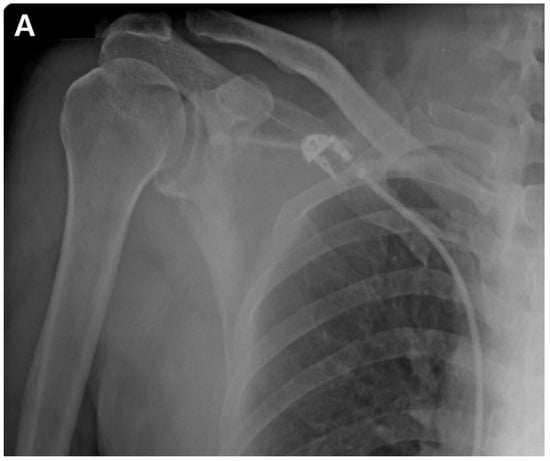

A postoperative scar was observed on the superior aspect along the distal clavicle and acromion, without definite tenderness, swelling, or redness. Preoperatively, the ROM of the affected shoulder was 90° for active forward flexion, 90° for abduction, 40° for external rotation, and at a sacral level for internal rotation. The passive and active ranges of motion were identical, attributed to the predominant cause of pain being stiffness rather than weakness. The visual analog scale (VAS) score was 4, the American Shoulder and Elbow Surgeons (ASES) score was 51, and the Constant–Murley Score (CMS) was 48. Preoperative shoulder radiographs showed acceptable alignment and joint congruency, with no bony spurs or subchondral lesions. The anteroposterior and axillary views of the shoulder radiograph showed an acceptable status of acromioclavicular joint reduction without arthritic changes. Magnetic resonance imaging (MRI) showed incomplete signal changes in the supraspinatus tendon, without a bony structural abnormality (Figure 1). Given the patient’s persistent symptoms, which did not improve, the patient opted for an ACR with informed consent.

Figure 1.

(A). Preoperative plain anteroposterior radiograph. Acromioclavicular joint alignment was acceptable with no arthritic changes. The glenohumeral joint showed adequate joint space and congruency. (B). Oblique coronal T2 fat-suppressed magnetic resonance imaging (MRI). MRI of the right shoulder showed a thickened axillary pouch with normal hypointense joint capsule. The supraspinatus tendon had high signal variation with intact continuity.